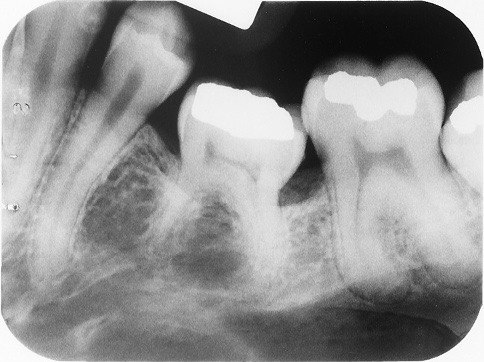

1. What is the condition in the distal surface of the tooth # 4.6?

2. What is the condition in the distal surface of the tooth # 4.7?